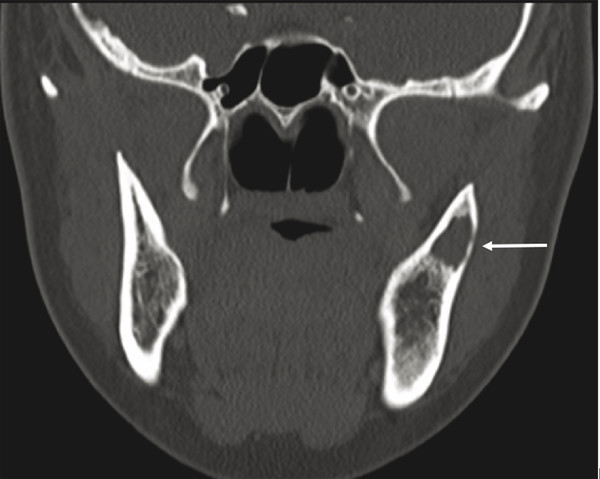

Finally, the nasopalatine duct cyst (NPDC) is a nonodontogenic developmental cyst that is usually found incidentally in the anterior maxilla in the area of the incisive canal. It can become painful, especially if secondarily infected. Radiographically, on an occlusal plain film radiograph, one finds a midline heart-shaped unilocular radiolucency. The lesion often is symmetric and is present in the anterior maxilla along the length of the incisive canal (Fig. 9‑5). Treatment comprises enucleation and curettage, with recurrence being very rare.